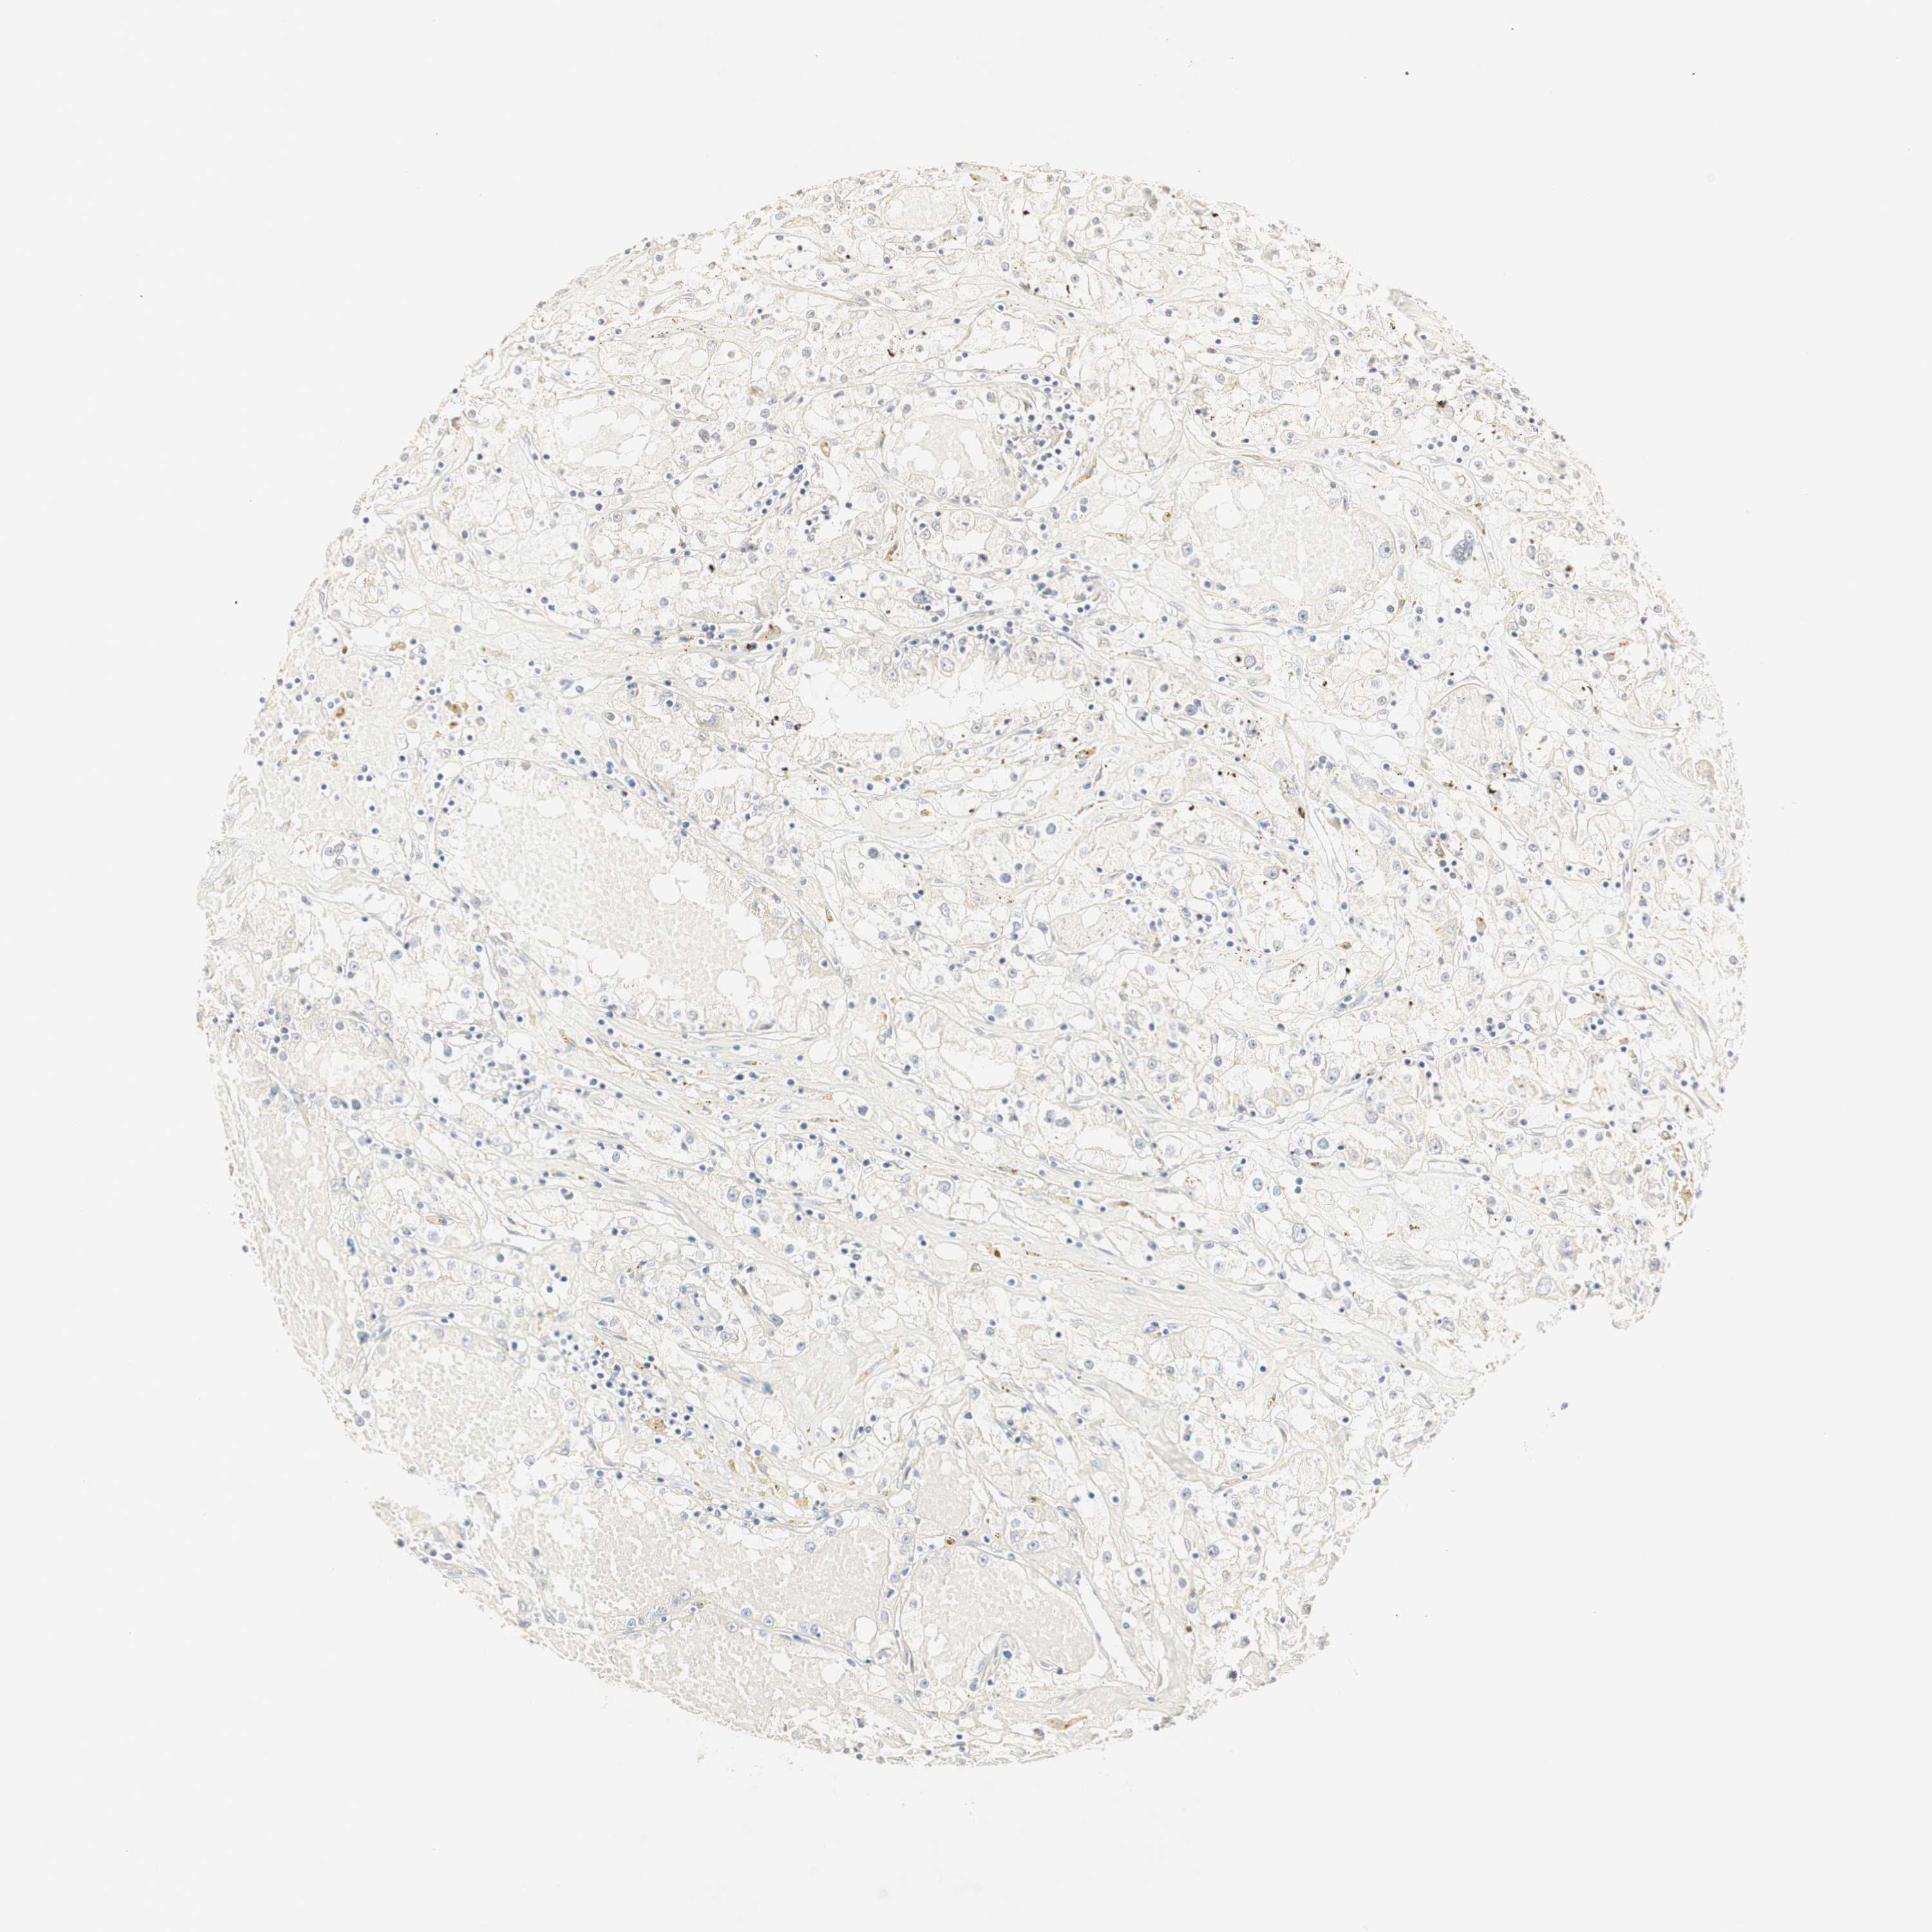

KIDNEY RENAL CLEAR CELL CARCINOMA (VALIDATION) - Interactive survival scatter ploti

The Survival Scatter plot shows the clinical status (i.e. dead or alive) for all individuals in the patient cohort, based on the same data that underlies the corresponding Kaplan-Meier plots. Patients that are alive at last time for follow-up are shown in blue and patients who have died during the study are shown in red.

The x-axis shows the expression levels (FPKM) of the investigated gene in the tumor tissue at the time of diagnosis. The y-axis shows the follow-up time after diagnosis (years). Both axes are complimented with kernel density curves demonstrating the data density over the axes. The top density plot shows the expression levels (FPKM) distribution among dead (red) and alive patients (blue). The right density plot shows the data density of the survived years of dead patients with high and low expression levels respectively, stratified using the cutoff indicated by the vertical dashed line through the Survival Scatter plot. This cutoff is automatically defined based on the FPKM cutoff that minimizes the p-score. The cutoff can be changed by dragging the vertical line or by entering a cutoff value in the square labeled "Current cut-off".

Under the Survival Scatter plot the p-score landscape (black curve; left axis) is shown together with dead median separation (red curve; right axis). Dead median separation is the difference in median mRNA expression between patients who have died with high and low expression, respectively. It is calculated as follows: median FPKM expression of dead patients with high expression - median FPKM expression of dead patients with low expression. This is intended to aid the user in visually exploring custom cutoffs and the associated p-scores and dead median separation.

Individual patient data is displayed and can be filtered by clicking on one or more of the category buttons on the top of the page. Categories describing expression level and patient information include: high, low, alive, dead, female, male and tumor stages. The scale of the x-axis can be toggled between linear and log-scale by clicking on the "x log" button. Mouse-over function shows TCGA ID, patient information and mRNA expression (FPKM) for each patient.

& Survival analysisi

Kaplan-Meier plots summarize results from analysis of correlation between mRNA expression level and patient survival. Patients were divided based on level of expression into one of the two groups "low" (under cut off) or "high" (over cut off). X-axis shows time for survival (years) and y-axis shows the probability of survival, where 1.0 corresponds to 100 percent.

DSC2 is not prognostic in Kidney Renal Clear Cell Carcinoma (validation)

Best expression cut offi

Based on the FPKM value of each gene, patients were classified into two groups and association between prognosis (survival) and gene expression (FPKM) was examined. The best expression cut-off refers the FPKM value that yields maximal difference with regard to survival between the two groups at the lowest log-rank P-value. Best expression cut-off was selected based on survival analysis .

When clicking on this number, the vertical dashed line indicating cut-off, the interactive survival plot, and the Kaplan-Meier curve will be adjusted to show results based on the best expression cut-off.

: 11.22

P scorei

Log-rank P value for Kaplan-Meier plot showing results from analysis of correlation between mRNA expression level and patient survival.

N/A

5-year survival highi

5-year survival for patients with higher expression than the expression cutoff.

For melanoma and glioma, 3-year survival is shown.

5-year survival lowi

5-year survival for patients with lower expression than the expression cutoff.

TCGA RNA samplesi

RNA-seq data is reported as average FPKM (number Fragments Per Kilobase of exon per Million reads), generated by the The Cancer Genome Atlas (TCGA) .

Normal distribution across the dataset is visualized with box plots, shown as median and 25th and 75th percentiles. Points are displayed as outliers if they are above or below 1.5 times the interquartile range. FPKM values of the individual samples are presented next to the box plot.

Average pTPM 14.6

Number of samples 100